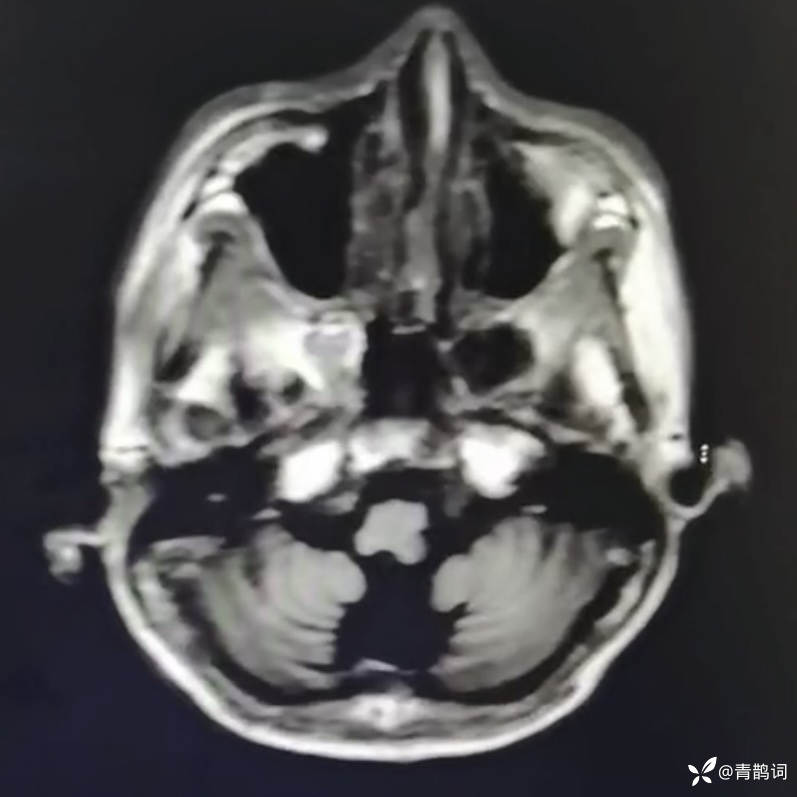

乐痴于医等 2人推荐简要病史:42岁男性,记忆力下降及听力下降一年余。既往体健,否认前驱感染病史。否认家族史。三个月前就诊于当地医院,自述腰穿脑脊液乳酸增高。现就诊于我院,查体记忆力下降,计算力下降,定时定向差,吟诗样语言。完善磁共振如下:

T1: